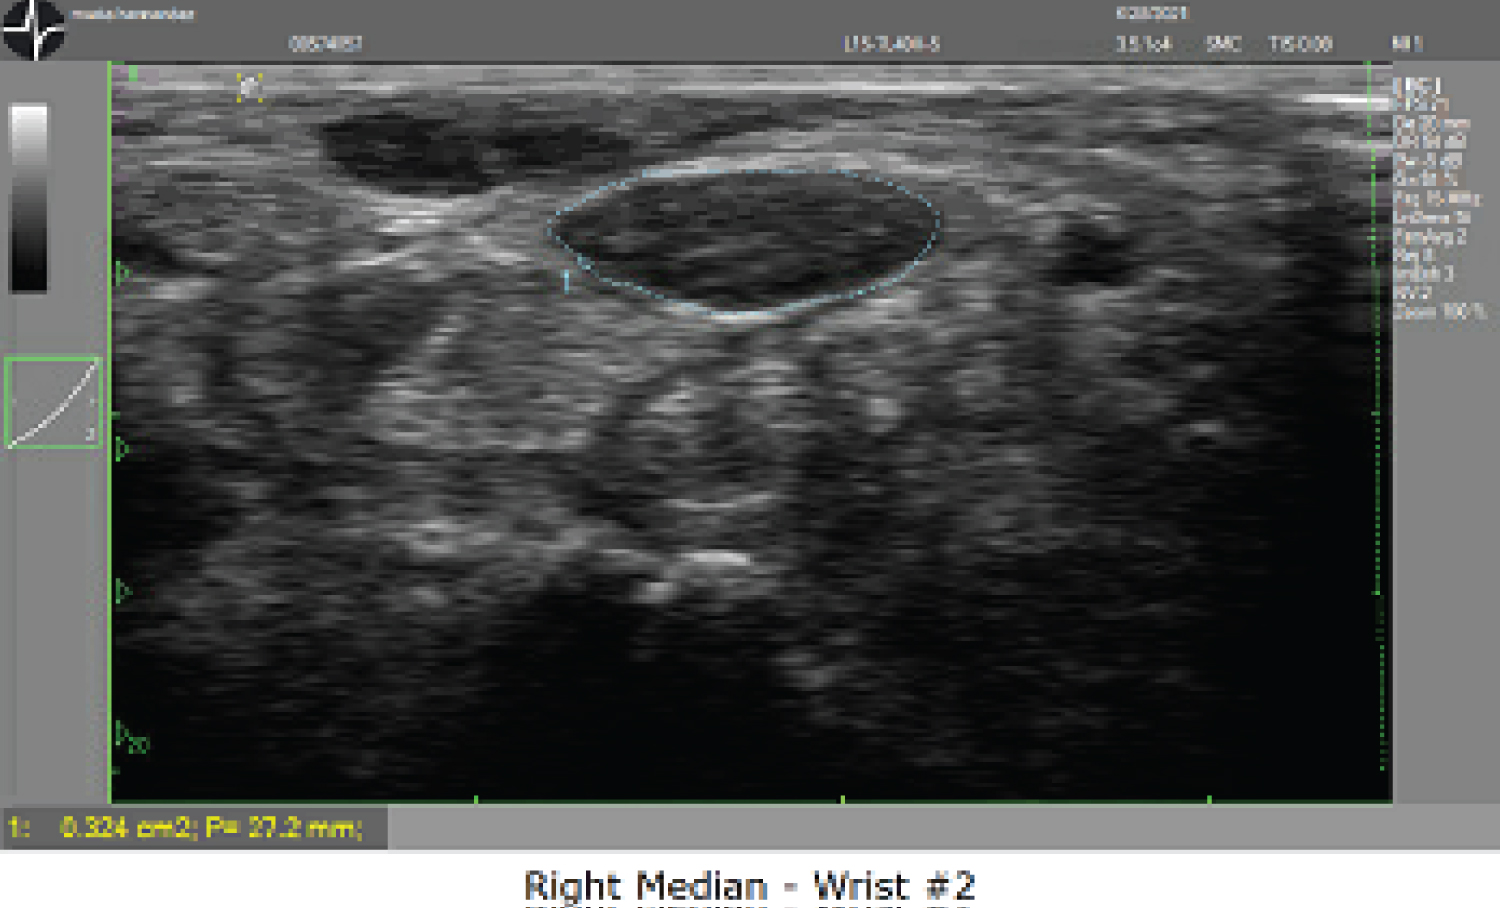

Our second patient is a 67-year-old female with chronic diffuse numbness and tingling in bilateral hands. Nightly wrist braces had provided only minimal symptomatic relief. Physical exam was significant for positive Tinel's and Durkan's test. EMG demonstrated severe bilateral median neuropathy with no sensory or motor response. A second lumbrical and interossei distal motor latency difference test (2L-INT DML) can be used to further characterize median mononeuropathy in patients with severe carpal tunnel syndrome to determine if there is any viable median nerve that may be amenable to surgery [25,26]. In this case, the test revealed very low amplitude and prolonged latency response of the median nerve. Ultrasound of the median nerves showed significant enlargement measuring 31.3 mm2 of the left median nerve cross sectional area and 32.4 mm2 of the right median nerve with no Doppler flow or masses within the median nerve appreciated (Figure 1B and Figure 1C). She underwent left and right carpal tunnel release surgery with significantly reduced numbness and tingling in both hands postoperatively (Table 2A, Table 2B, Figure 2 and Figure 3).

Figure 3B: Right Median - Wrist # 2. View Figure 3b